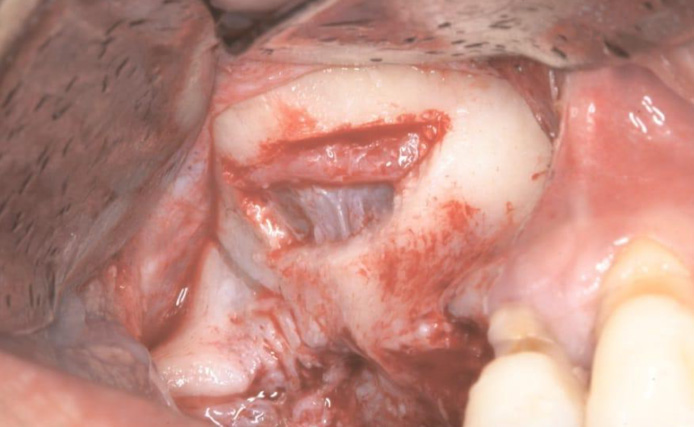

Одной из методик снижения риска повреждения мягких тканей и других структур, таких как нервные волокна и кровеносные сосуды (в том числе и альвеоло-антральная артерия) даже при случайном контакте во время проведения синус-лифтинга (рис 3), является использование ультразвуковых пьезохирургических устройств [2,21].

рис 3.jpg

Рисунок 3. Целостность мембраны Шнайдера и альвеоло-антральной артерии при проведении латеральной антротомии с помощью пьезохирургических насадок (фото Len Tolstunov. Horizontal Alveolar Ridge Augmentation in Implant Dentistry: A Surgical Manual).